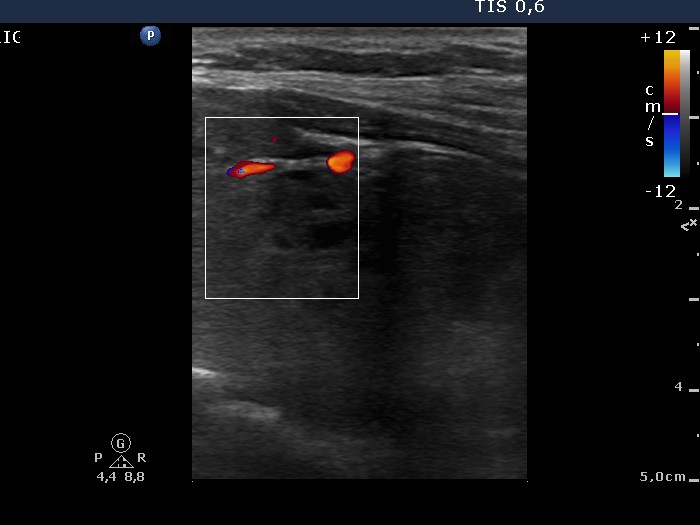

Ultraosonography: the left lobe presented a large nodule composed of several discrete lesions. The intranodular vascularization was increased.